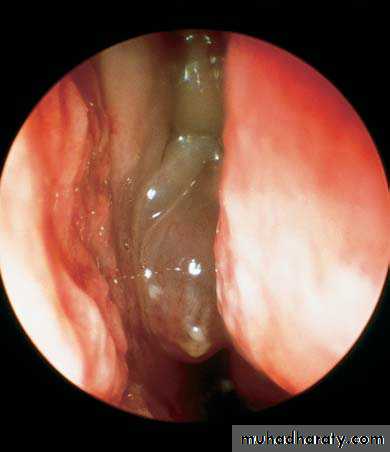

Purulent discharge from the middle meatus draining into the nasopharynx adjacent to the eustachian tube orifice.